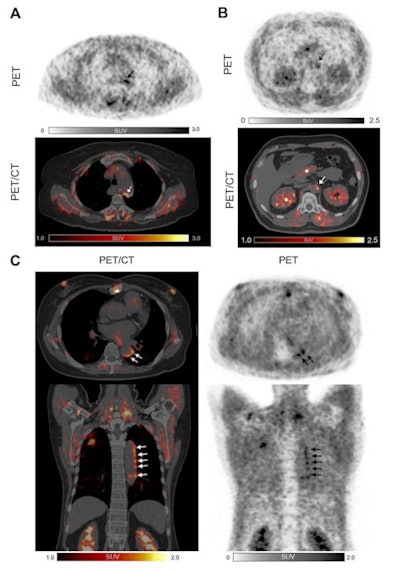

Three examples of Ga-68 FAPI uptake of active arterial segments. All three patients were over 60 years old with a history of hypertension and dyslipidemia. Patients A and C also had diabetes mellitus, and experienced myocardial infarction and percutaneous coronary intervention treatment. Patient A was obese (body mass index = 30) while patient B had a history of heavy smoking."To our knowledge, this is the first noninvasive study to describe the expression of FAP in the human arterial walls via Ga-68 FAPI-PET/CT imaging," they wrote.